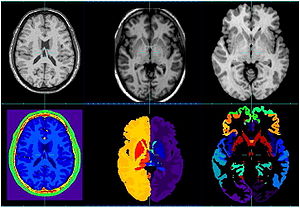

- 7.2 Comparison of Acute and Chronic Traumatic Brain Injury Using Semi-automatic Multimodal Segmentation of MR Volumes